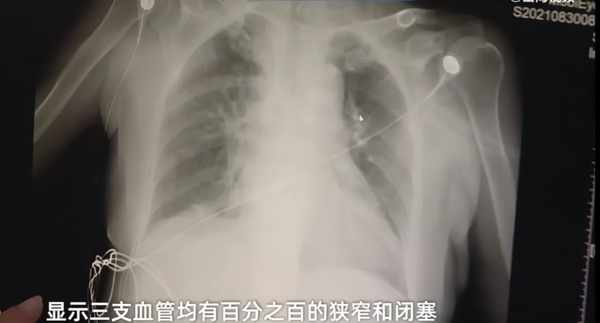

經過一系列檢查,這些患者已經明顯出現急性的廣泛前壁心肌梗死,隨後醫生又給患者進行了急性冠脈造影檢查,顯示三支血管均有百分之百的狹窄和閉塞。

(新聞截圖)